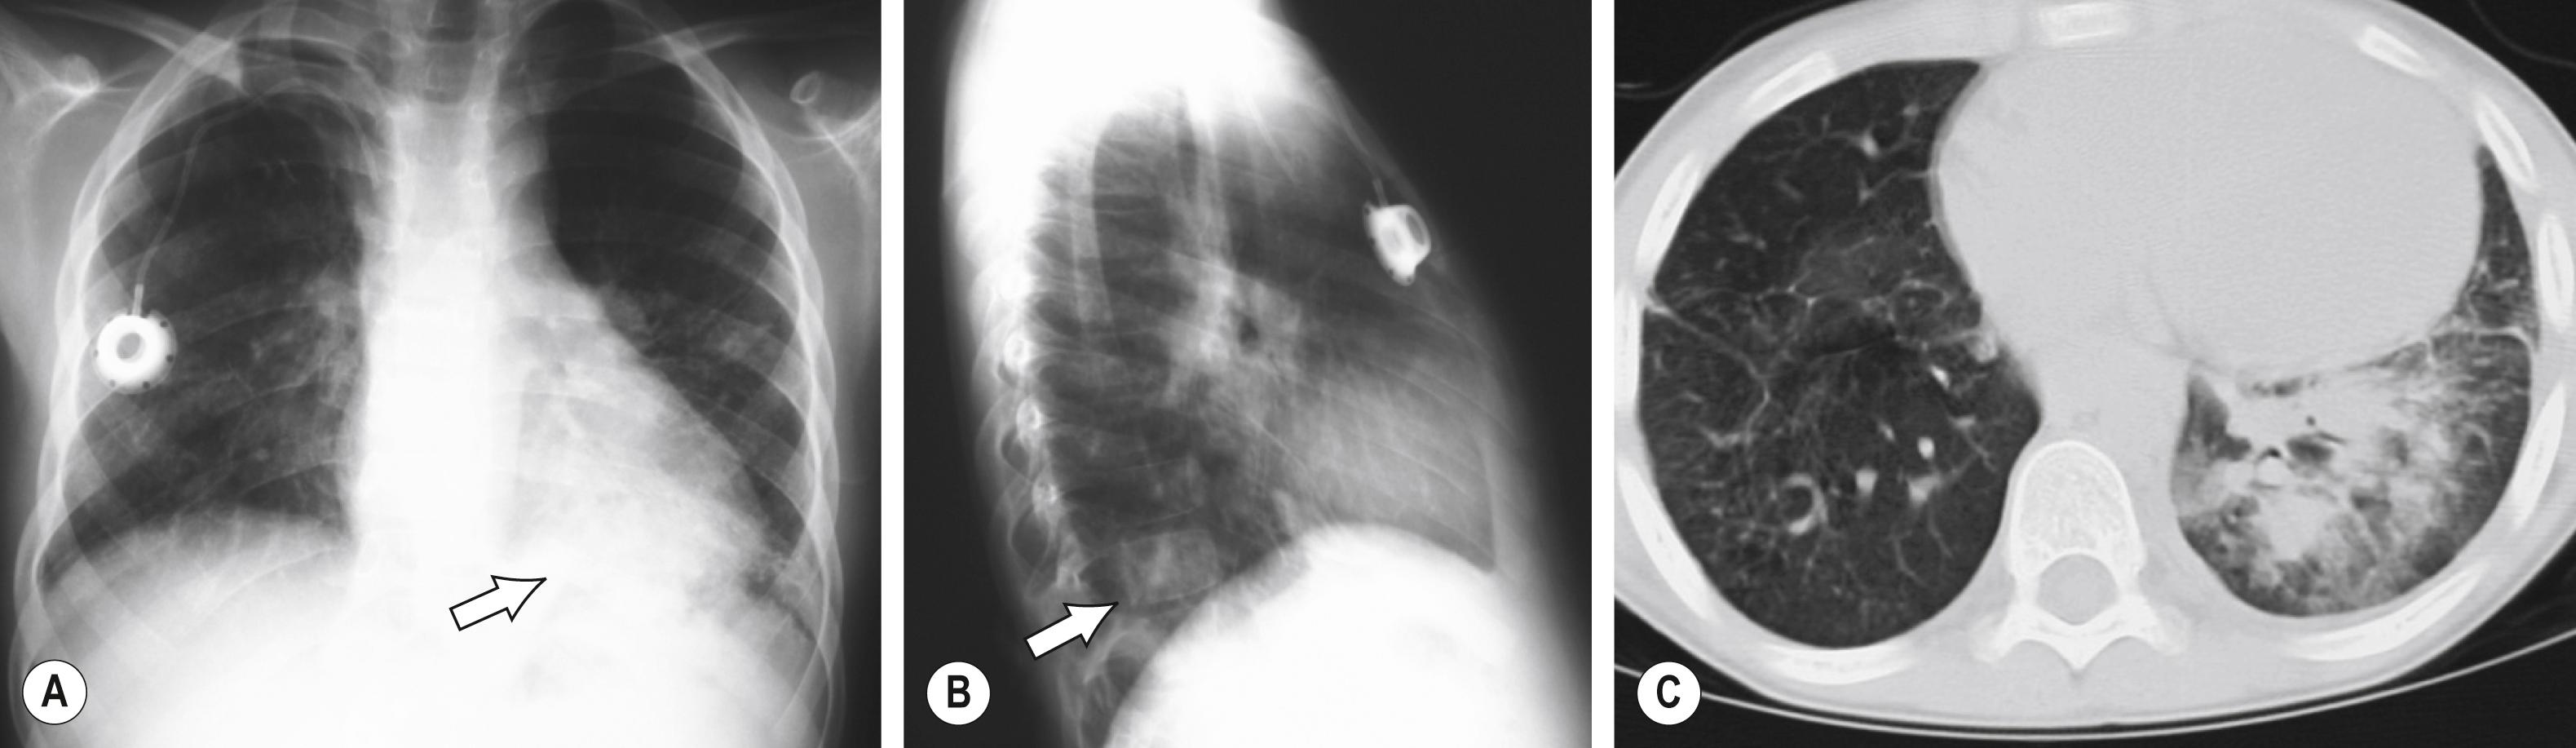

Abnormal acute inflammatory responses contribute to ineffective wound healing that is characteristic of these conditions. At sites of injury, histologic examination can show disordered inflammatory responses, such as combinations of acute and chronic inflammation ( Fig. 104.1 ) or poor accumulation of inflammatory cells. In some instances, abnormal inflammatory responses—rather than infection—are the major cause of pathology.

FIGURE 104.1, Pyogranuloma (acute inflammatory cells within granulomatous inflammatory response) (arrow) in the lung of patient with chronic granulomatous disease and Aspergillus spp. pneumonia.

FIGURE 104.2, Chest radiograph and chest CT scan of a 7-year-old child with chronic granulomatous disease with fever and dry cough. Plain films show a retrocardiac left lower lobe infiltrate (arrow) (A), which appears small on the lateral view (arrow) (B). (C) CT demonstrated more extensive disease throughout the left lower lobe. Burkholderia cepacia was isolated from the open-lung biopsy. Because this child had an episode of pneumonia caused by the same organism 12 months previously, the exposure history was more intensively examined, revealing that the child had a favorite outdoor activity of pulling up wild onions.

The importance of obtaining specimens for culture from sites of infection cannot be overemphasized; the variety of potential agents and the complicated nature of management require definitive knowledge for optimal treatment. Cultures of blood, urine, and cerebrospinal fluid (if appropriate), as well as cultures from all infected sites, should be obtained before initiation of treatment. Surgical or imaging-guided biopsy is performed for deep infection ( Fig. 104.2 ).